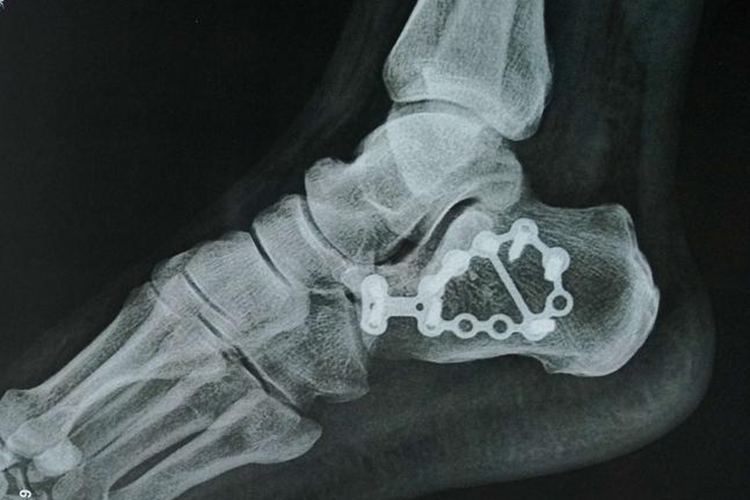

脚后跟骨折,医学上称为跟骨骨折,是一种较为常见的足部损伤。对于接受手术治疗的跟骨骨折患者而言,手术后恢复正常走路的时间一般需要3至6个月,但这一时间范围并非绝对,它受到多种因素的影响,如骨折的严重程度等。

2、手术方式和术后治疗:手术方式的选择、手术技术的精湛程度以及术后是否采取了有效的治疗措施,如固定、康复锻炼等,都会对恢复时间产生影响。良好的手术和术后治疗能够加速骨折愈合,缩短恢复时间,可短至3个月左右。